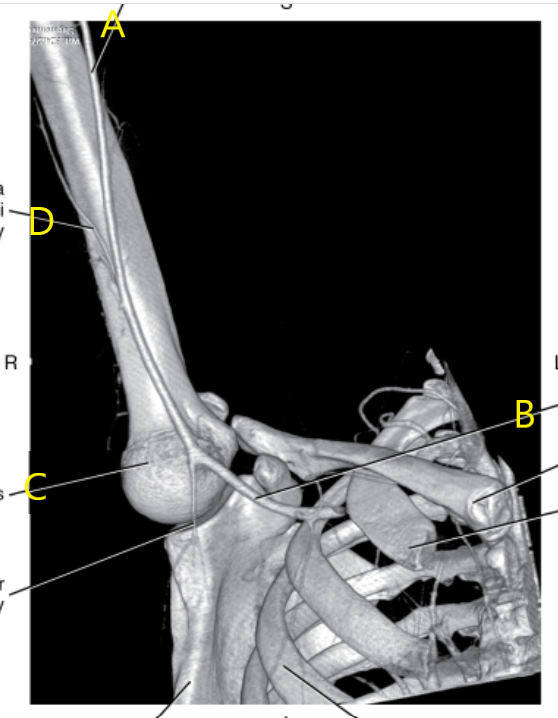

What is letter A?

Brachial artery

What is letter B pointing to ?

Humerus

What is letter C pointing to ?

Coracoid process

What is # 1 ?

What is # 2 ?

Acromion Process

What anatomy is # 2 ?

Ulna

Scapula

The anterior surface of the scapula, the____________ _________, is flat and slightly concave.